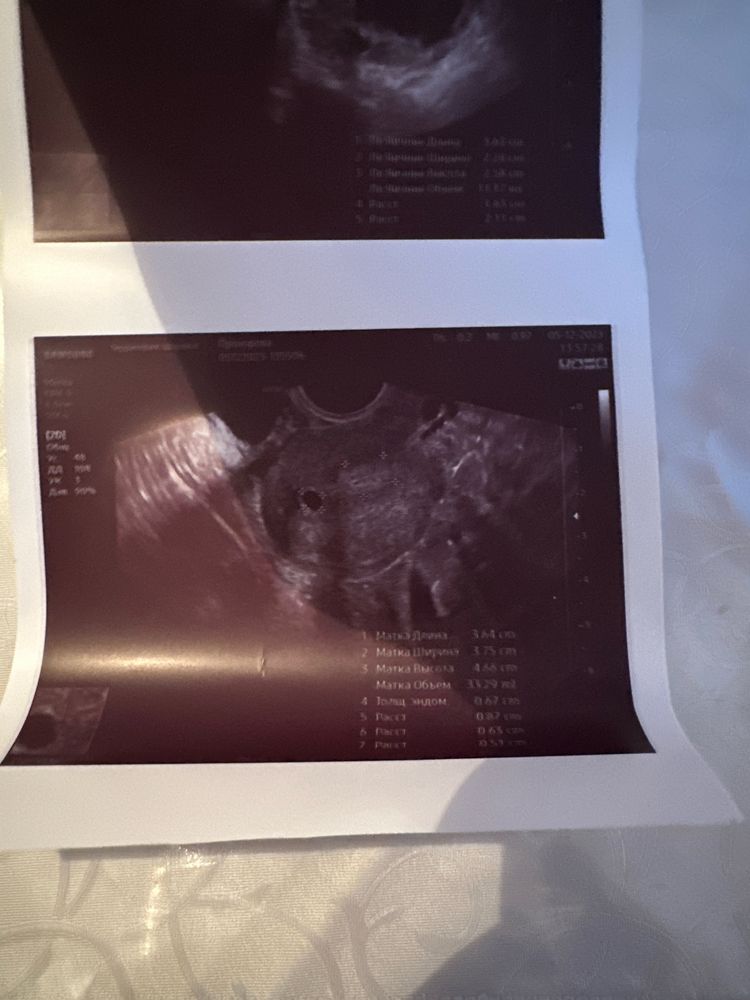

Решили сделать узи, смотрим, а там желтое тело 16 х 21 мм с активными переферическим кровотоком по ЦДК(заключение врача)

Фото узи прилагаю